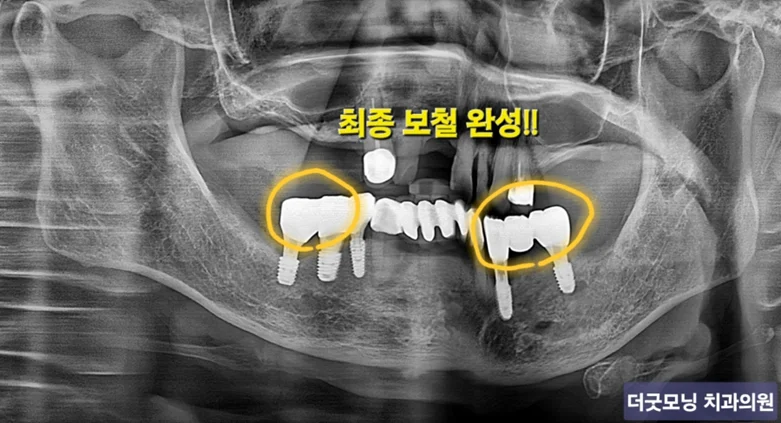

STEP 5 — 보철 완성

디지털 스캔을 활용하여 정밀 보철을 제작하고 장착하였습니다. 환자분도 결과에 매우 만족하셨습니다.

최종 보철 완성 후 임상 사진